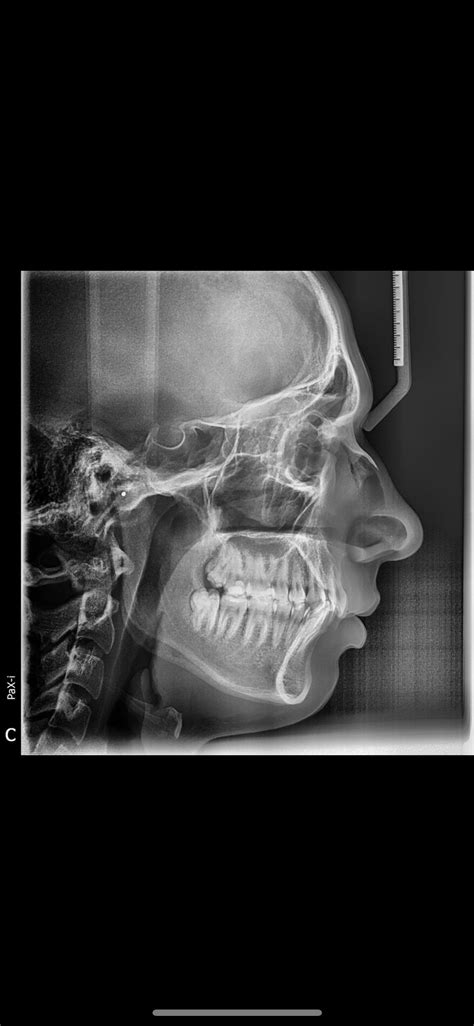

Understanding the differences between the maxilla and mandible is crucial for anyone studying anatomy, dentistry, or related fields. These two bones play pivotal roles in the structure and function of the human skull, particularly in the facial region. The maxilla, often referred to as the upper jaw, and the mandible, known as the lower jaw, have distinct characteristics and functions that are essential for various physiological processes.

The maxilla is a paired bone that forms the upper jaw and a significant portion of the facial skeleton. It is one of the strongest bones in the face and serves multiple critical functions. The maxilla is composed of several parts, including the body, alveolar process, palatine process, and zygomatic process.

The body of the maxilla is the main part that forms the upper jaw. It contains the maxillary sinuses, which are air-filled cavities that help to lighten the skull and resonate the voice. The alveolar process is the part of the maxilla that contains the sockets for the upper teeth. The palatine process forms the anterior portion of the hard palate, which separates the oral and nasal cavities. The zygomatic process articulates with the zygomatic bone to form the cheekbone.

Anatomy of the Mandible

The mandible, or lower jaw, is the largest and strongest bone in the face. It is a single, U-shaped bone that forms the lower jaw and provides attachment for the muscles of mastication. The mandible consists of several key parts, including the body, ramus, coronoid process, condylar process, and mental foramen.

The body of the mandible is the horizontal part that contains the sockets for the lower teeth. The ramus is the vertical part that extends upward from the body and articulates with the temporal bone at the temporomandibular joint. The coronoid process is a triangular projection on the anterior surface of the ramus, which serves as an attachment site for the temporalis muscle. The condylar process is a rounded projection on the posterior surface of the ramus, which articulates with the temporal bone to form the temporomandibular joint. The mental foramen is an opening on the lateral surface of the body, through which the mental nerve and vessels pass.